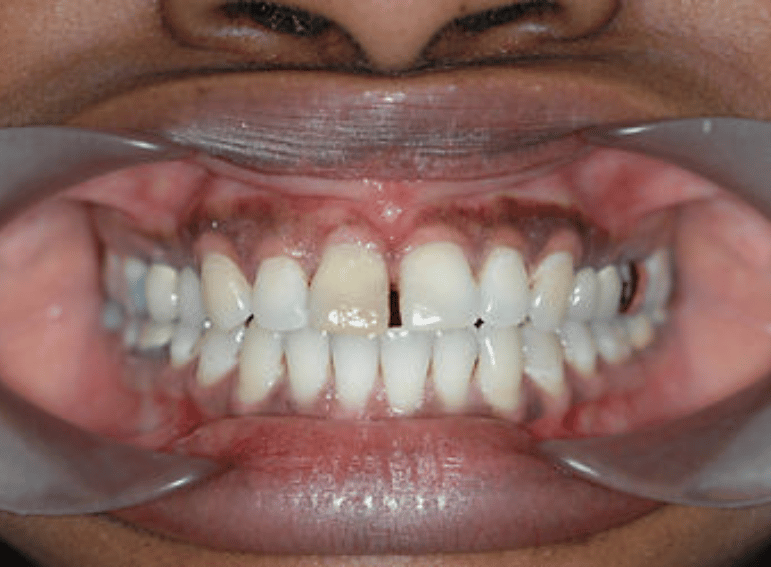

Internal and external whitening of a discoloured central incisor.